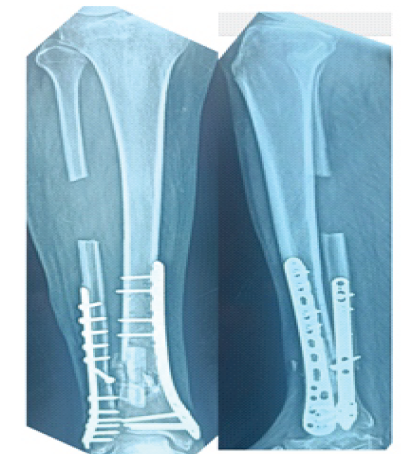

After 1 year and 3 months, the patient presented to the author’s outpatient department. On examination, the surgical scar was healthy. Tenderness is present at the fracture site. Range of motion of ankle was normal. Patient was walking with crutches. However, no signs of union are present on the radiograph and there are no signs of implant failure (Fig. 3). The case is diagnosed as aseptic non-union distal tibia with implants in situ.

Figure 3: One and half year post-operative X-ray after initial fixation showing non-union